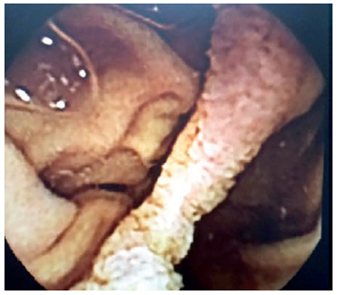

Para continuar con el estudio, se usó una cápsula endoscópica para buscar sangrado oculto manifiesto, la cual demostró una probable lesión en la segunda porción del duodeno (figura 2). Por esta razón, se practicó una tercera endoscopia de vías digestivas altas que evidenció un divertículo duodenal y una duplicación duodenal tubular, sin alteraciones de la mucosa (figura 3). En las vías digestivas altas se evidenció una duplicación tubular del duodeno en su tercera porción (figura 4).